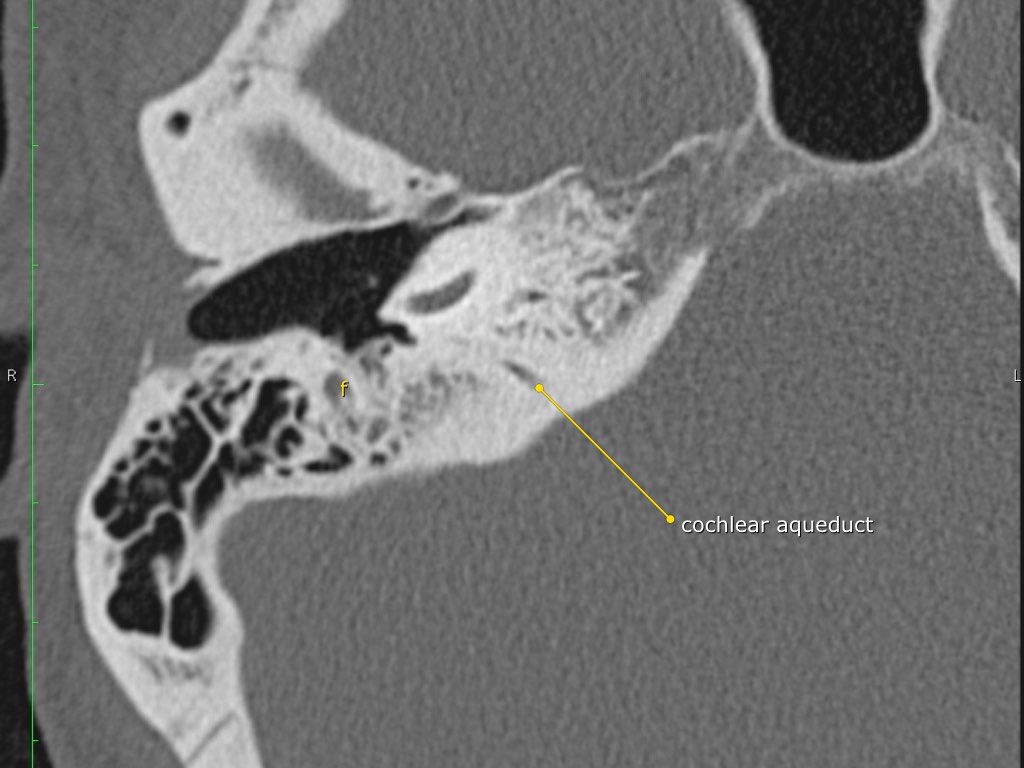

Trong bài tổng quan này, chúng tôi trình bày giải phẫu bình thường trên mặt phẳng cắt ngang (axial) và mặt phẳng cắt đứng ngang (coronal) của xương thái dương thông qua việc duyệt qua các hình ảnh.

Một số cấu trúc được thảo luận chi tiết hơn với trọng tâm là các bệnh lý liên quan.

Giải phẫu xương đá trên mặt phẳng cắt ngang (Axial)

Cuộn qua các hình ảnh.